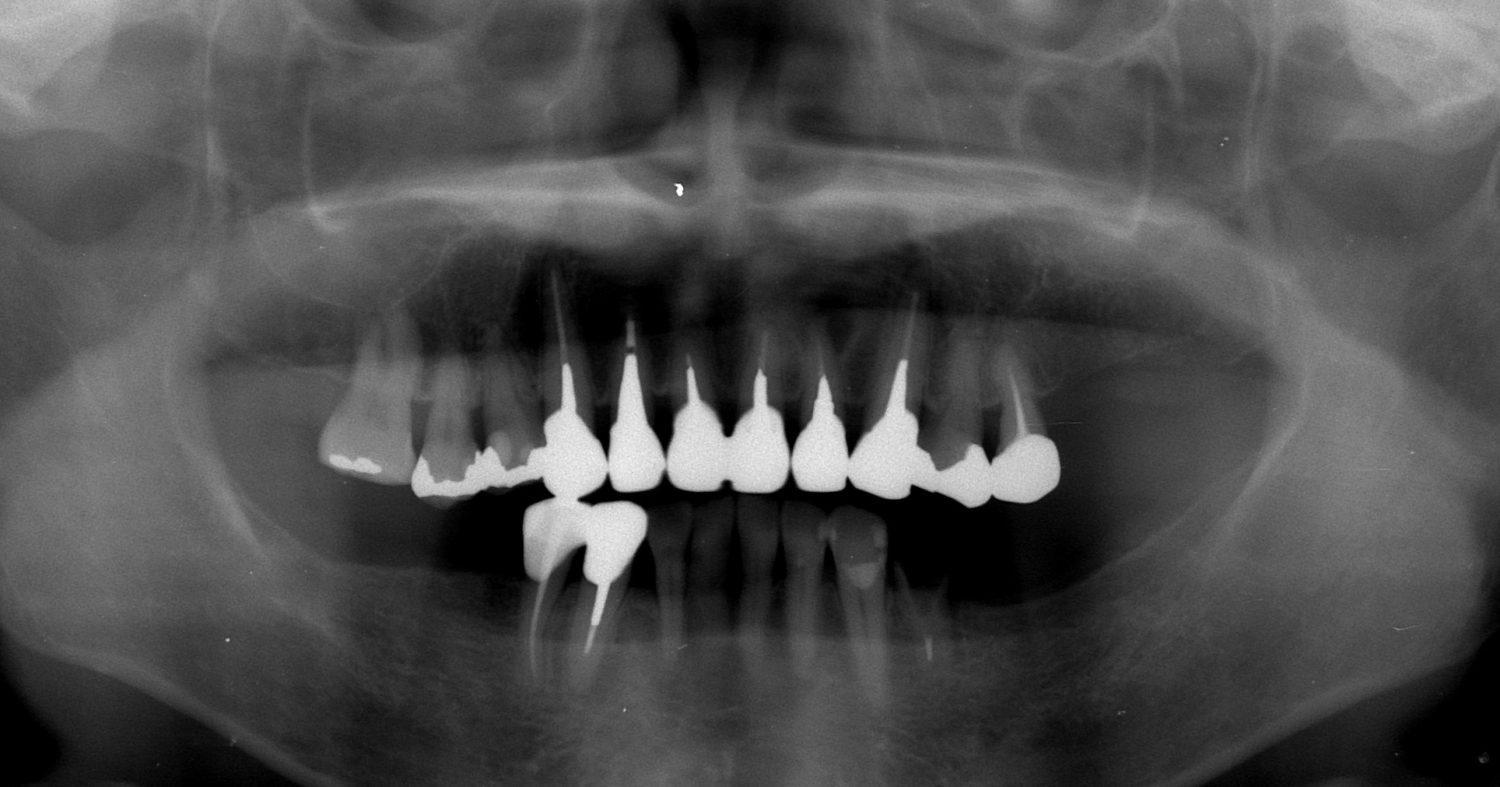

外科矯正治療・インプラント治療・セラミック治療の症例紹介(三隅歯科クリニック)

三隅 賢祐(三隅歯科クリニック)

症例詳細

| 主訴 | 50代男性 右上の歯と歯茎が痛い。どこで噛んでいいのか分からないので夜も眠れない |

| 治療内容 | 外科矯正治療・インプラント治療・セラミック治療を行いました。 |

| 治療費 | 4,500,000円(税込み) |

| 治療期間 | 4年(矯正治療期間 3年) |

| 治療回数 | 60回 |

| 想定されたリスク | 顎骨の変形があったので、全身麻酔下による外科処置が必要になり、身体的、精神的負担が増す可能性がありました。 清掃状況によっては矯正中にむし歯が発生するリスクがありました。 |